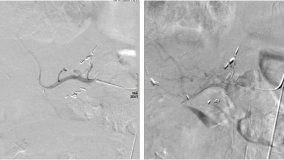

• digital subtraction angiography, which uses computer subtraction of background images to enhance arterial blood-flow;